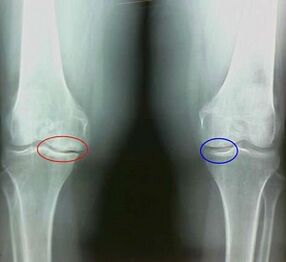

For example, what is the difference between arthritis and the arthrosis of the knee wrist?In addition to arthritis, Sinovi shell of articulated tissues.This causes an increase in temperature in the compound.

Shared swollen, it develops a persistent pain syndrome, intensification during the movement.In addition to arthrosis, pain occurs only after physical activity, you can hear the characteristic mater or clicks in the compound, a gradual compound is deformed and loses mobility.

Arthrosis is developed gradually and not noticeable in the early stages.It is often taken for physical fatigue.The chronic form of arthrosis is also called osteoarthrosis.When asked what is worse - arthrosis or osteoarthrosis, the answer is obvious.The last option is due to the development of arthrosis and its acute form.

Among the symptoms of arthrosis, the following are characterized:

- Pain appears after physical activity, with sudden movements, turns, preferences, after vacation, passes pain;

- The characteristic crumb in the joints is noticed;

- After a long rest pain, which passes within 15-20 minutes of mobility (this is associated with stagnant phenomena occurring in the compound);

- worried about the nightly boring pain of pain that occurs due to venous stagnation;

- The inflammatory form of pathology is accompanied by edema and pain;

- The wrist is deformed, his mobility is declining.